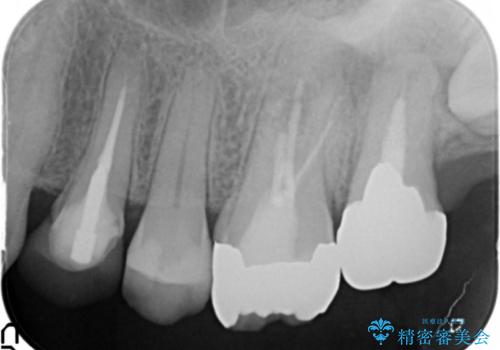

精査したところ、奥歯(左上67)の根尖部に位置した歯茎に瘻孔(膿の出口)ができており、CTを撮影し確認すると奥歯2本(左上67)の根尖病変は大きくつながっていました。

銀座しらゆり歯科の林院長による精密根管治療を受けて頂いたのち、メタルボンドクラウンによる補綴を行いました。